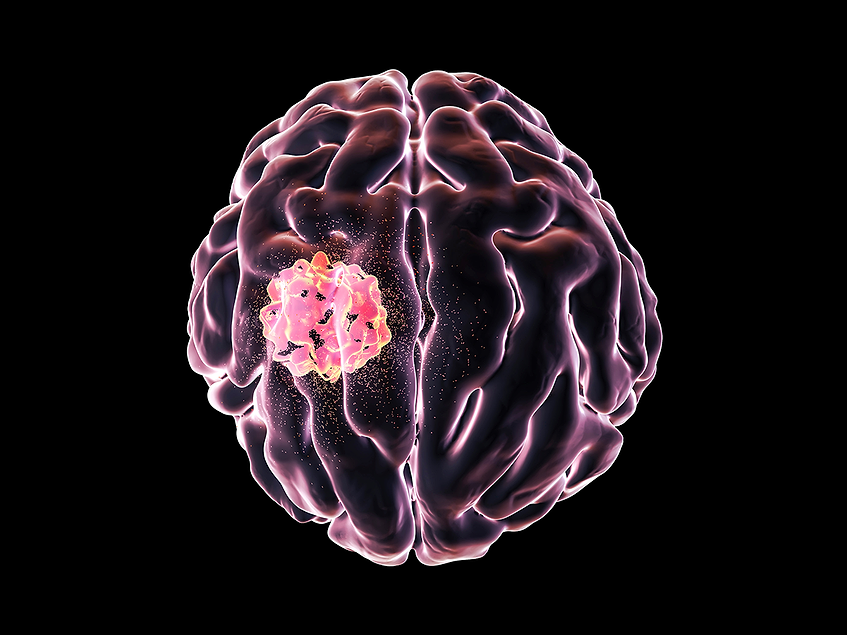

FDA issues CRL for Telix's glioma imaging agent, wants more data

The U.S. FDA issued a complete response letter (CRL) to Telix Pharmaceuticals Ltd. for its NDA for glioma imaging agent, TLX-101-CDx (floretyrosine F18 or 18F-FET, Pixclara), citing the need for additional confirmatory clinical evidence. BioWorld BioWorld …